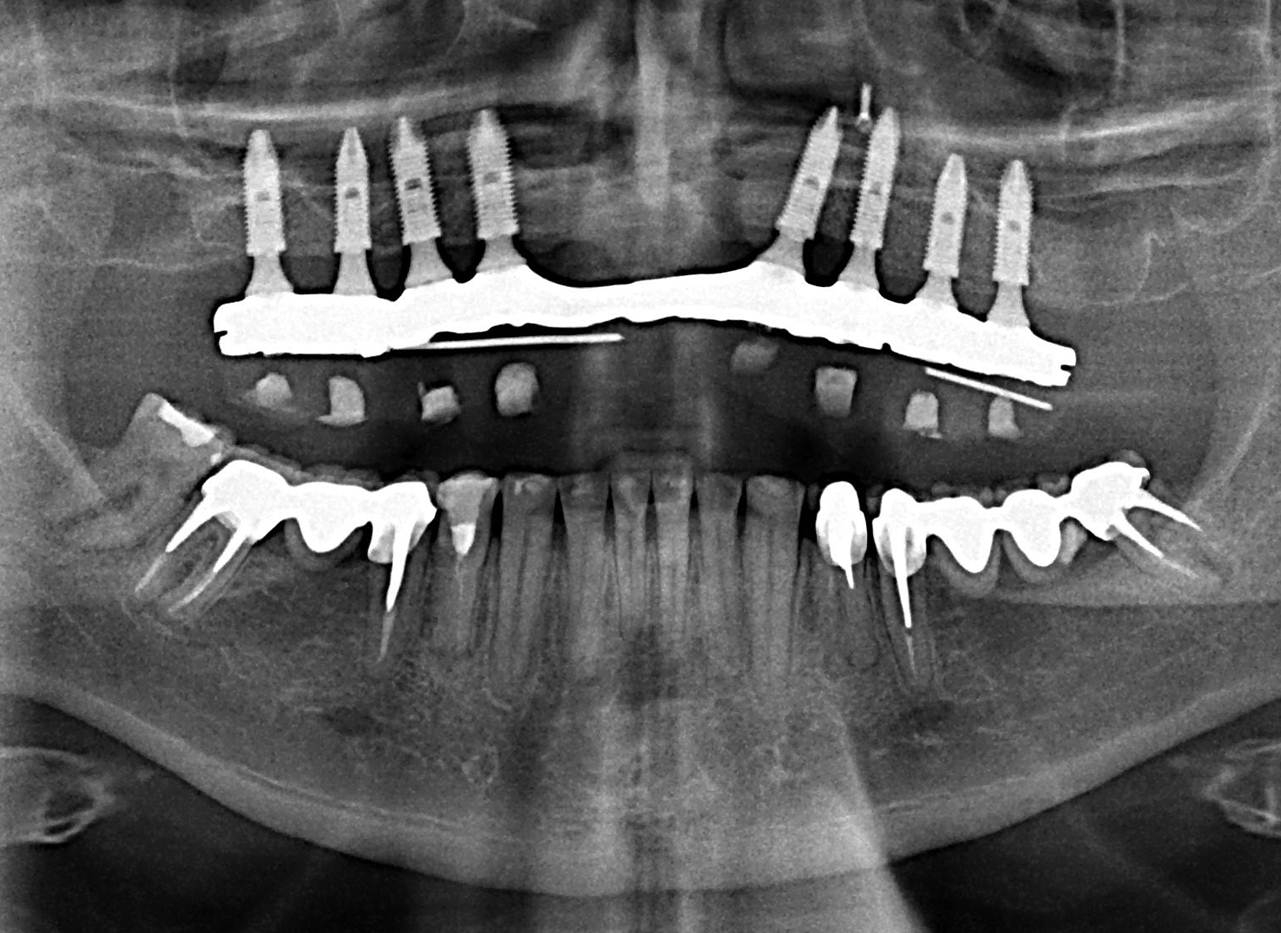

Raio X com a prótese fixa em resina instalada sobre implantes Cone Morse - Clínica Cliniface

Raio X com a prótese fixa em resina instalada sobre implantes Cone Morse